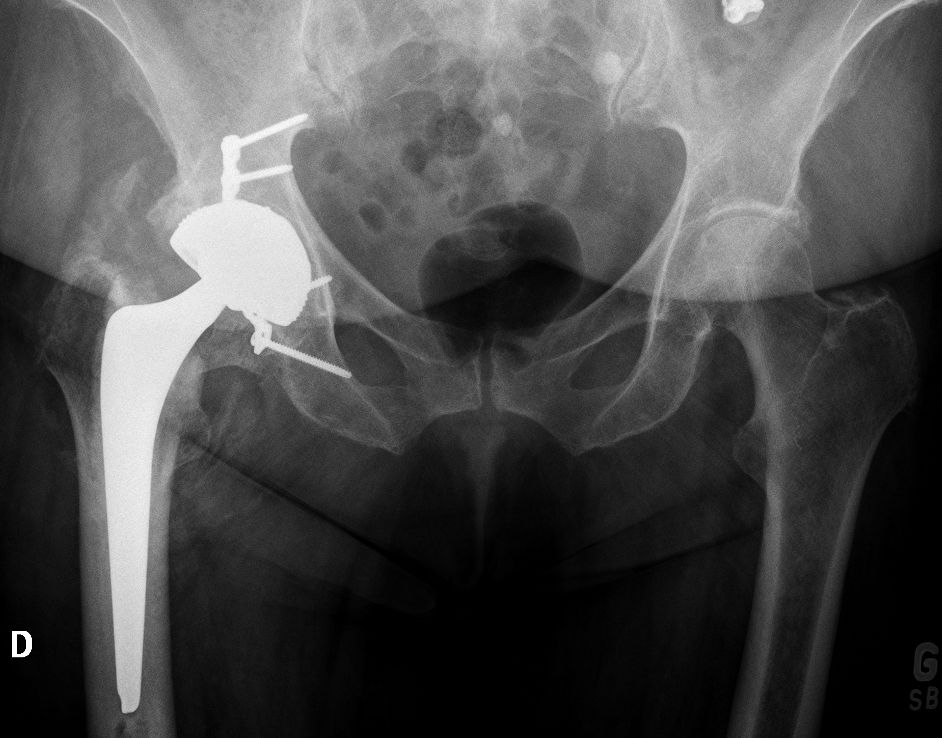

For the older, more sedentary and those with a shorter life expectancy, DM LDH THA is the ideal alternative (Figs 7 and 8).

The DM implant design combines the stability benefits of LDH with wear rates that are significantly lower than those of fixed bearing implants[33,34]. Loving et al., in a simulator study under multiple test conditions (impingement, abrasion, loss of mobility of the insert), showed that performance in terms of wear was dictated mainly by a smaller joint and by the polyethylene material used. For the most severe tests, a 75% lower wear rate was observed compared to a fixed insert of conventional polyethylene sterilized under gamma rays in an inert atmosphere[35]. Given the lower cost and absence of the potential drawbacks of hard-on-hard bearings such as noise, fracture, and trunnionosis, DM should be considered for all patients over 65 years.